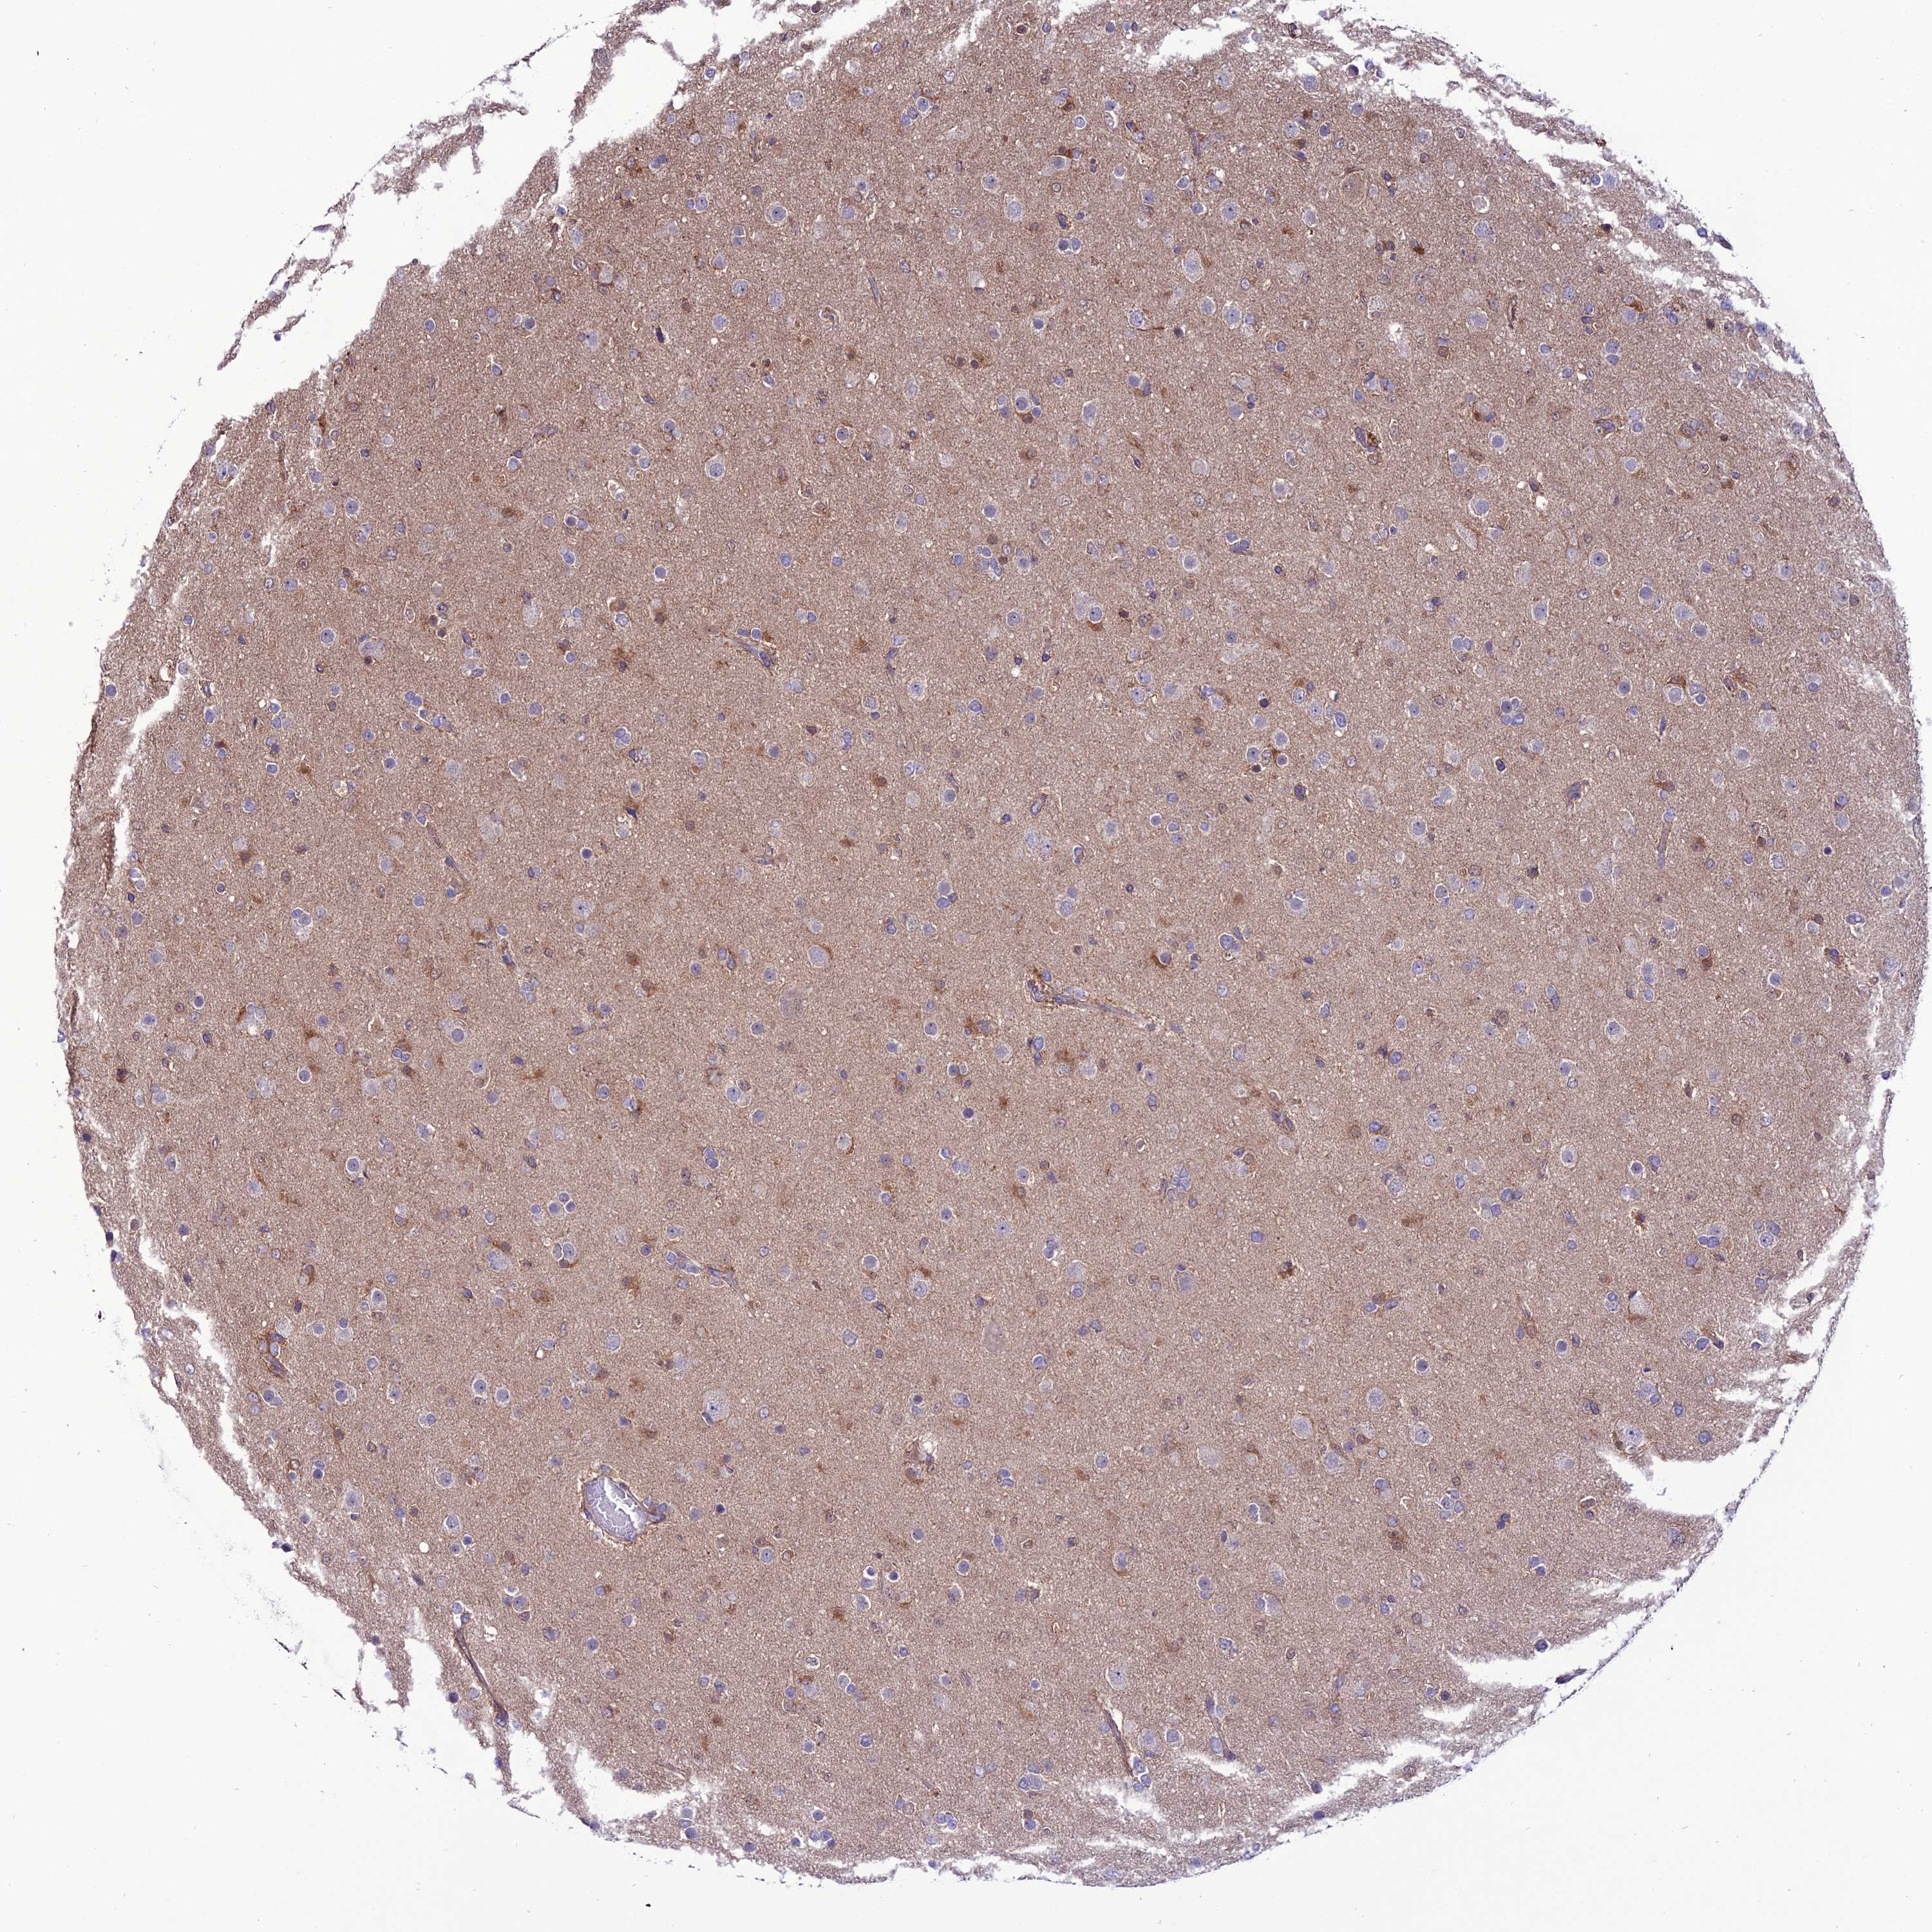

GLIOMA - Protein expressioni

A mouse-over function shows sample information and annotation data. Click on an image to view it in a full screen mode. Samples can be filtered based on level of antibody staining by selecting one or several of the following categories: high, medium, low and not detected. The assay and annotation is described here.

Note that samples used for immunohistochemistry by the Human Protein Atlas do not correspond to samples in the TCGA dataset.

Antibody stainingi

Antibody staining in the annotated cell types in the current human tissue is reported as not detected, low, medium, or high, based on conventional immunohistochemistry profiling in selected tissues. This score is based on the combination of the staining intensity and fraction of stained cells.

Each image is clickable and will lead to virtual microscopy that enables deeper exploration of all samples and also displays staining intensity scores, fraction scores and subcellular localization as well as patient and tissue information for each sample.

Antibody HPA040765

Staining

High

Medium

Low

Not detected

Intensity

Strong

Moderate

Weak

Negative

Quantity

>75%

75%-25%

<25%

None

Location

Nuclear

Cytoplasmic/membranous

Cytoplasmic/membranous,nuclear

Glioma, malignant, High grade

Glioma, malignant, Low grade